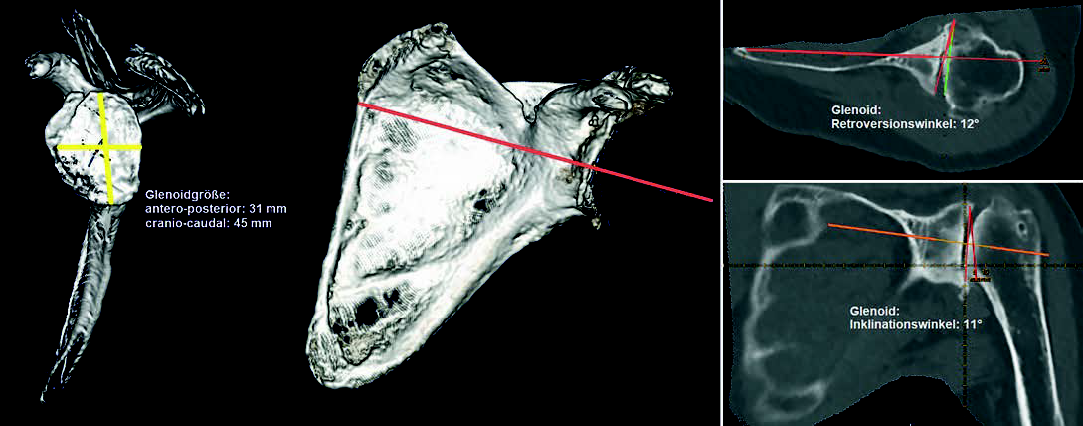

even a 3D plan. However, 3D planning is based on CT images, and unfortunately I do not always have a suitable CT with the appropriate thin-slice resolution and dimensions (entire scapula and epicondyles), because many patients only have an MRI with them, which usually does not show the end points of the affected bones that are actually required, and they assume that this is sufficient.

MRI, but with significantly more limited information than 3D planning with reproducible reference planes in the scapula planes and humeral axes.

two-dimensional planning on the conventional X-ray is not sufficient for the shoulder. For exact positioning, three-dimensional planning based on CT data, with standardized reference planes as the starting position for reproducible planning, offers a good possibility that extends to preoperative dynamic simulation.